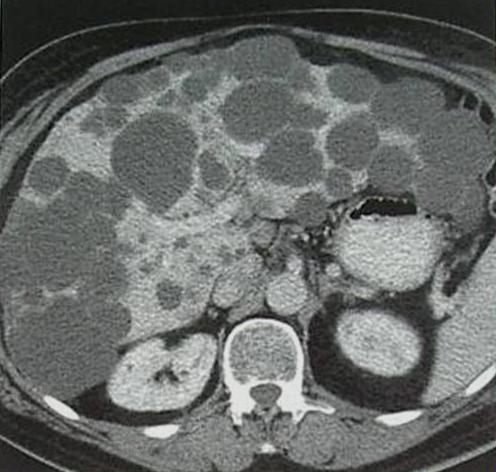

The simple cyst (Figure 16) indicates a difference from the multicystic liver only in the number of the cysts. Conversely, the polycystic liver (Figure 17) is an autosomal dominant inheritant disorder, in which the cystic conversion can be present in up to 70-80% of the liver parenchyma due to the large number of the cysts. It often accompanies with polycystic kidneys, whilst the entire polycystic syndrome – if also polycystic affection of the pancreas is also associated – occurs very rarely.

Figure 17: Polycystic liver, contrast enhanced CT